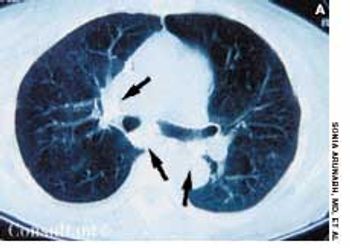

A 2-month history of cough sent a 62-year-old woman for medical evaluation. The patient denied fever, chills, and rigors but reported seeing streaks of blood in her sputum during the past month. The patient had undergone a right nephrectomy 4 years earlier for renal cell carcinoma.